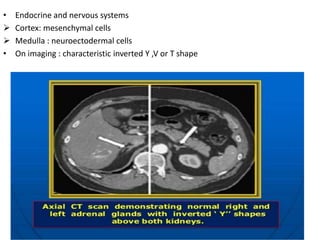

• Endocrine and nervous systems

 Cortex: mesenchymal cells

 Medulla : neuroectodermal cells

• On imaging : characteristic inverted Y ,V or T shape